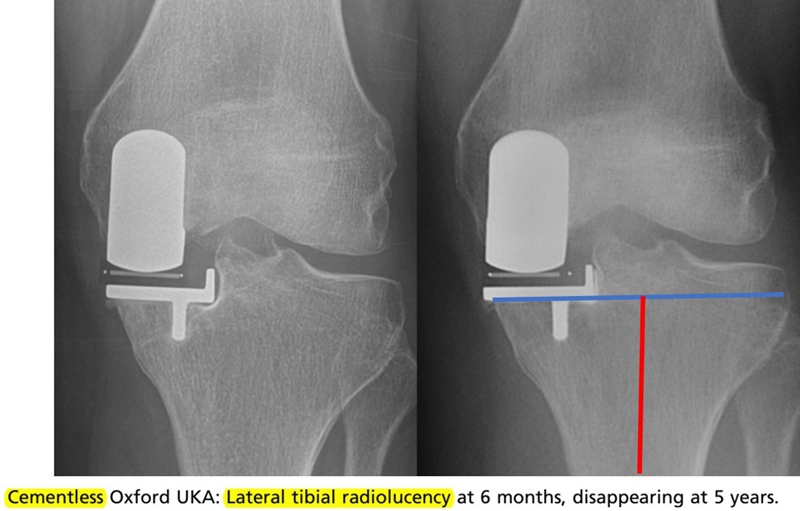

其他技术引导下的胫骨截骨:导航引导截骨,PSI引导截骨,AI、机器人引导截骨。